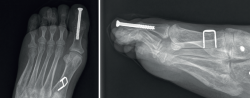

Figura 8. Varón, 22 años. Afecto de pie cavo neurológico severo, secundario a hemiparesia izquierda tras traumatismo craneoencefálico. Pie cavo varo irreductible. Realización de triple artrodesis con transferencia tendinosa (tibial posterior) para su corrección (se observa el arpón de reinserción ósea en cuña en la proyección lateral radiográfica).